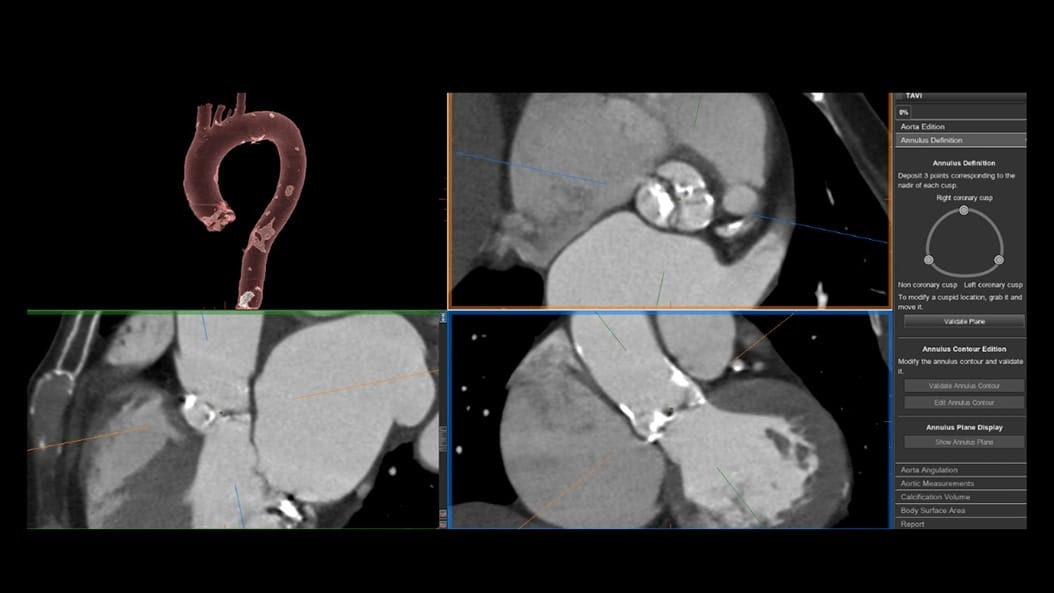

CT-Guided Interventional Care

Since becoming an important step in the patient care pathway and heart care guidelines, CT images are an invaluable tool in the cath lab, guiding procedures for precise personalized care.

Growth in CT imaging for structural heart (TAVR, TMVR, LAAO, etc.)⁴